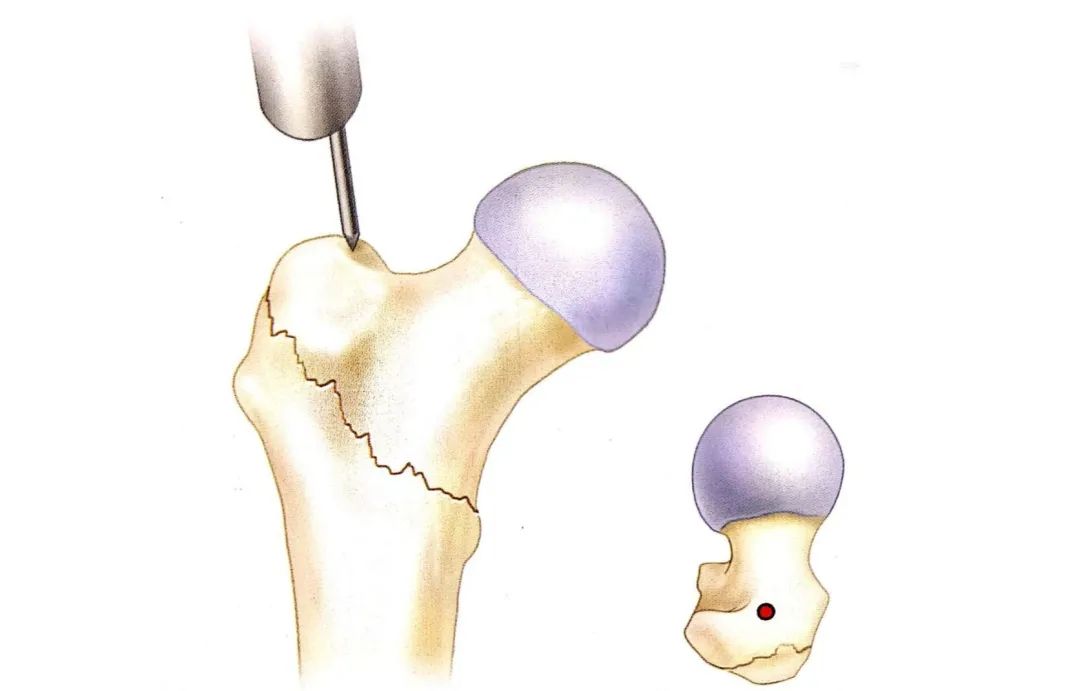

我院首例应用intertan髓内钉固定治疗严重粉碎复杂的股骨粗隆间由骨一

intertan髓内钉治疗中青年粗隆间骨折

intertan在股骨粗隆间骨折的应用及技术要点

髓内钉intertan与重建钉治疗股骨近端骨折的疗效比较